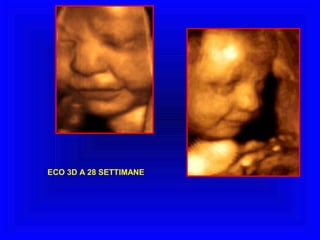

ECO 3D A 28 SETTIMANE

ECO 3D A28 SETTIMANE